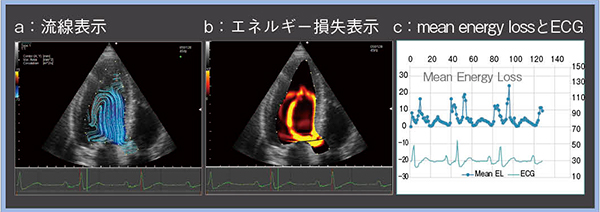

心臓の血流動態解析としては4D flow MRIなどがあるが,これを心エコーで実現したのがVFMである。VFMは,カラードプラ情報と心筋壁の運動情報から,流体の質量保存則に基づき超音波ビームと直交方向の速度成分を求め,血流速度ベクトルを表示する9)。VFMを用いて計測する指標の一つとしてエネルギー損失(energy loss)がある。隣り合う血流速度ベクトルの差が大きいほどエネルギー損失が大きくなり,左室内のエネルギー損失の大きさの違いによって心機能を詳しく評価できると考えられている。

図5,6は,重症の大動脈弁狭窄症の経カテーテル大動脈弁留置術(TAVI)前後のVFM画像である。VFMのエネルギー損失表示では,損失の程度が大きいほど濃い色で表現されるが,TAVI後の画像は色がやや薄く,数値的にも明らかにエネルギー損失が減少していた(図6 b,c)。TMFも確認したところ,TAVI前後でほぼ変化は見られないことから,TMFで確認できない変化をVFMのエネルギー損失表示ではとらえていると考えられる。

VFMは再現性良くエネルギー損失を評価可能であり,TAVI後のエネルギー損失の改善を確認できるなど,血行動態の変化および心筋の効率的な仕事量を鋭敏にとらえられる可能性がある。

図5 VFMで計測したTAVI前のエネルギー損失

図6 VFMで計測したTAVI後のエネルギー損失